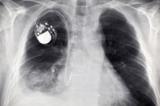

Швейцарские ученые произвели настоящий фурор на прошедшем в выходные ежегодном совещании Европейского общества кардиологов в Барселоне. Дело в том, что они представили новый кардиостимулятор, работающий без батареек...